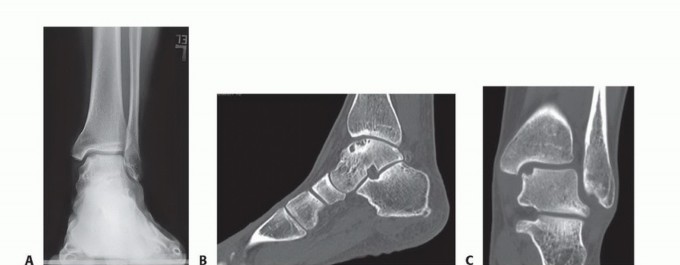

DEFINITION Medium-sized osteochondral defects of the talar dome May approach the talar shoulder (transition o…

DEFINITION Osteochondral lesions of the talus (OLT) are common conditions that can involve both the cartilage…